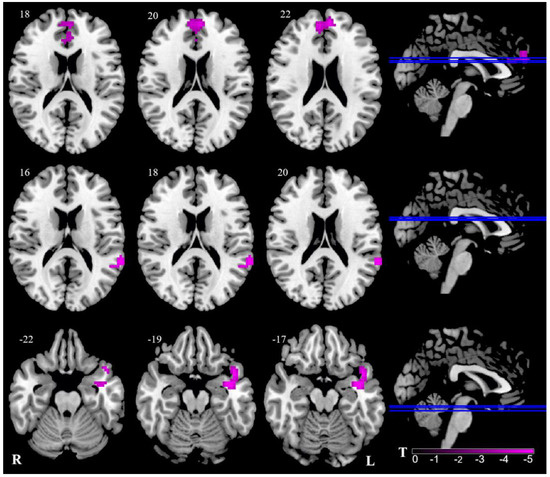

Two clusters showed bilaterally decreased ALFF values in the thalamus. Thus, we selected these two clusters as seeds for further FC analysis. The left thalamus showed significantly weaker FC with the bilateral medial prefrontal cortex (mPFC), the bilateral anterior cingulum cortex (ACC), the left superior/middle temporal gyrus, and the temporal pole in the VM group. Therefore, there was no significant difference between the right thalamus and other brain areas in the two groups. (Table 3, Figure 2).

Figure 2.

Abnormal FC of VM patients in contrast to HC. Pink signifies decreased ALFF. The axial image was overlaid on the transverse section of the MNI-152 standard anatomical image. Blue line represents the layers in the sagittal. Numbers indicate z slice. The color scale denotes the t-value. R, right; L, left.